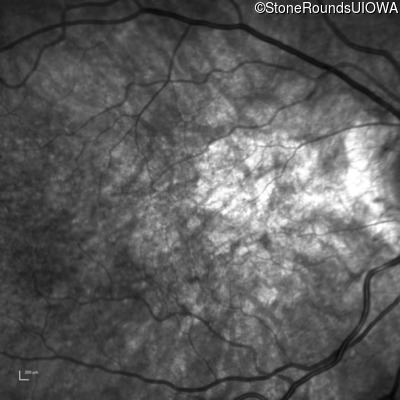

Pseudoxanthoma Elasticum (IID2)

Age at visit: 58 years

Diagnosis & molecular findings

Disease Gene Allele 1 variant(s) Allele 2 variant(s) Inheritance mode

Pseudoxanthoma Elasticum ABCC6 Gly928 del4tacGGCA IVS21+1 G>T AR